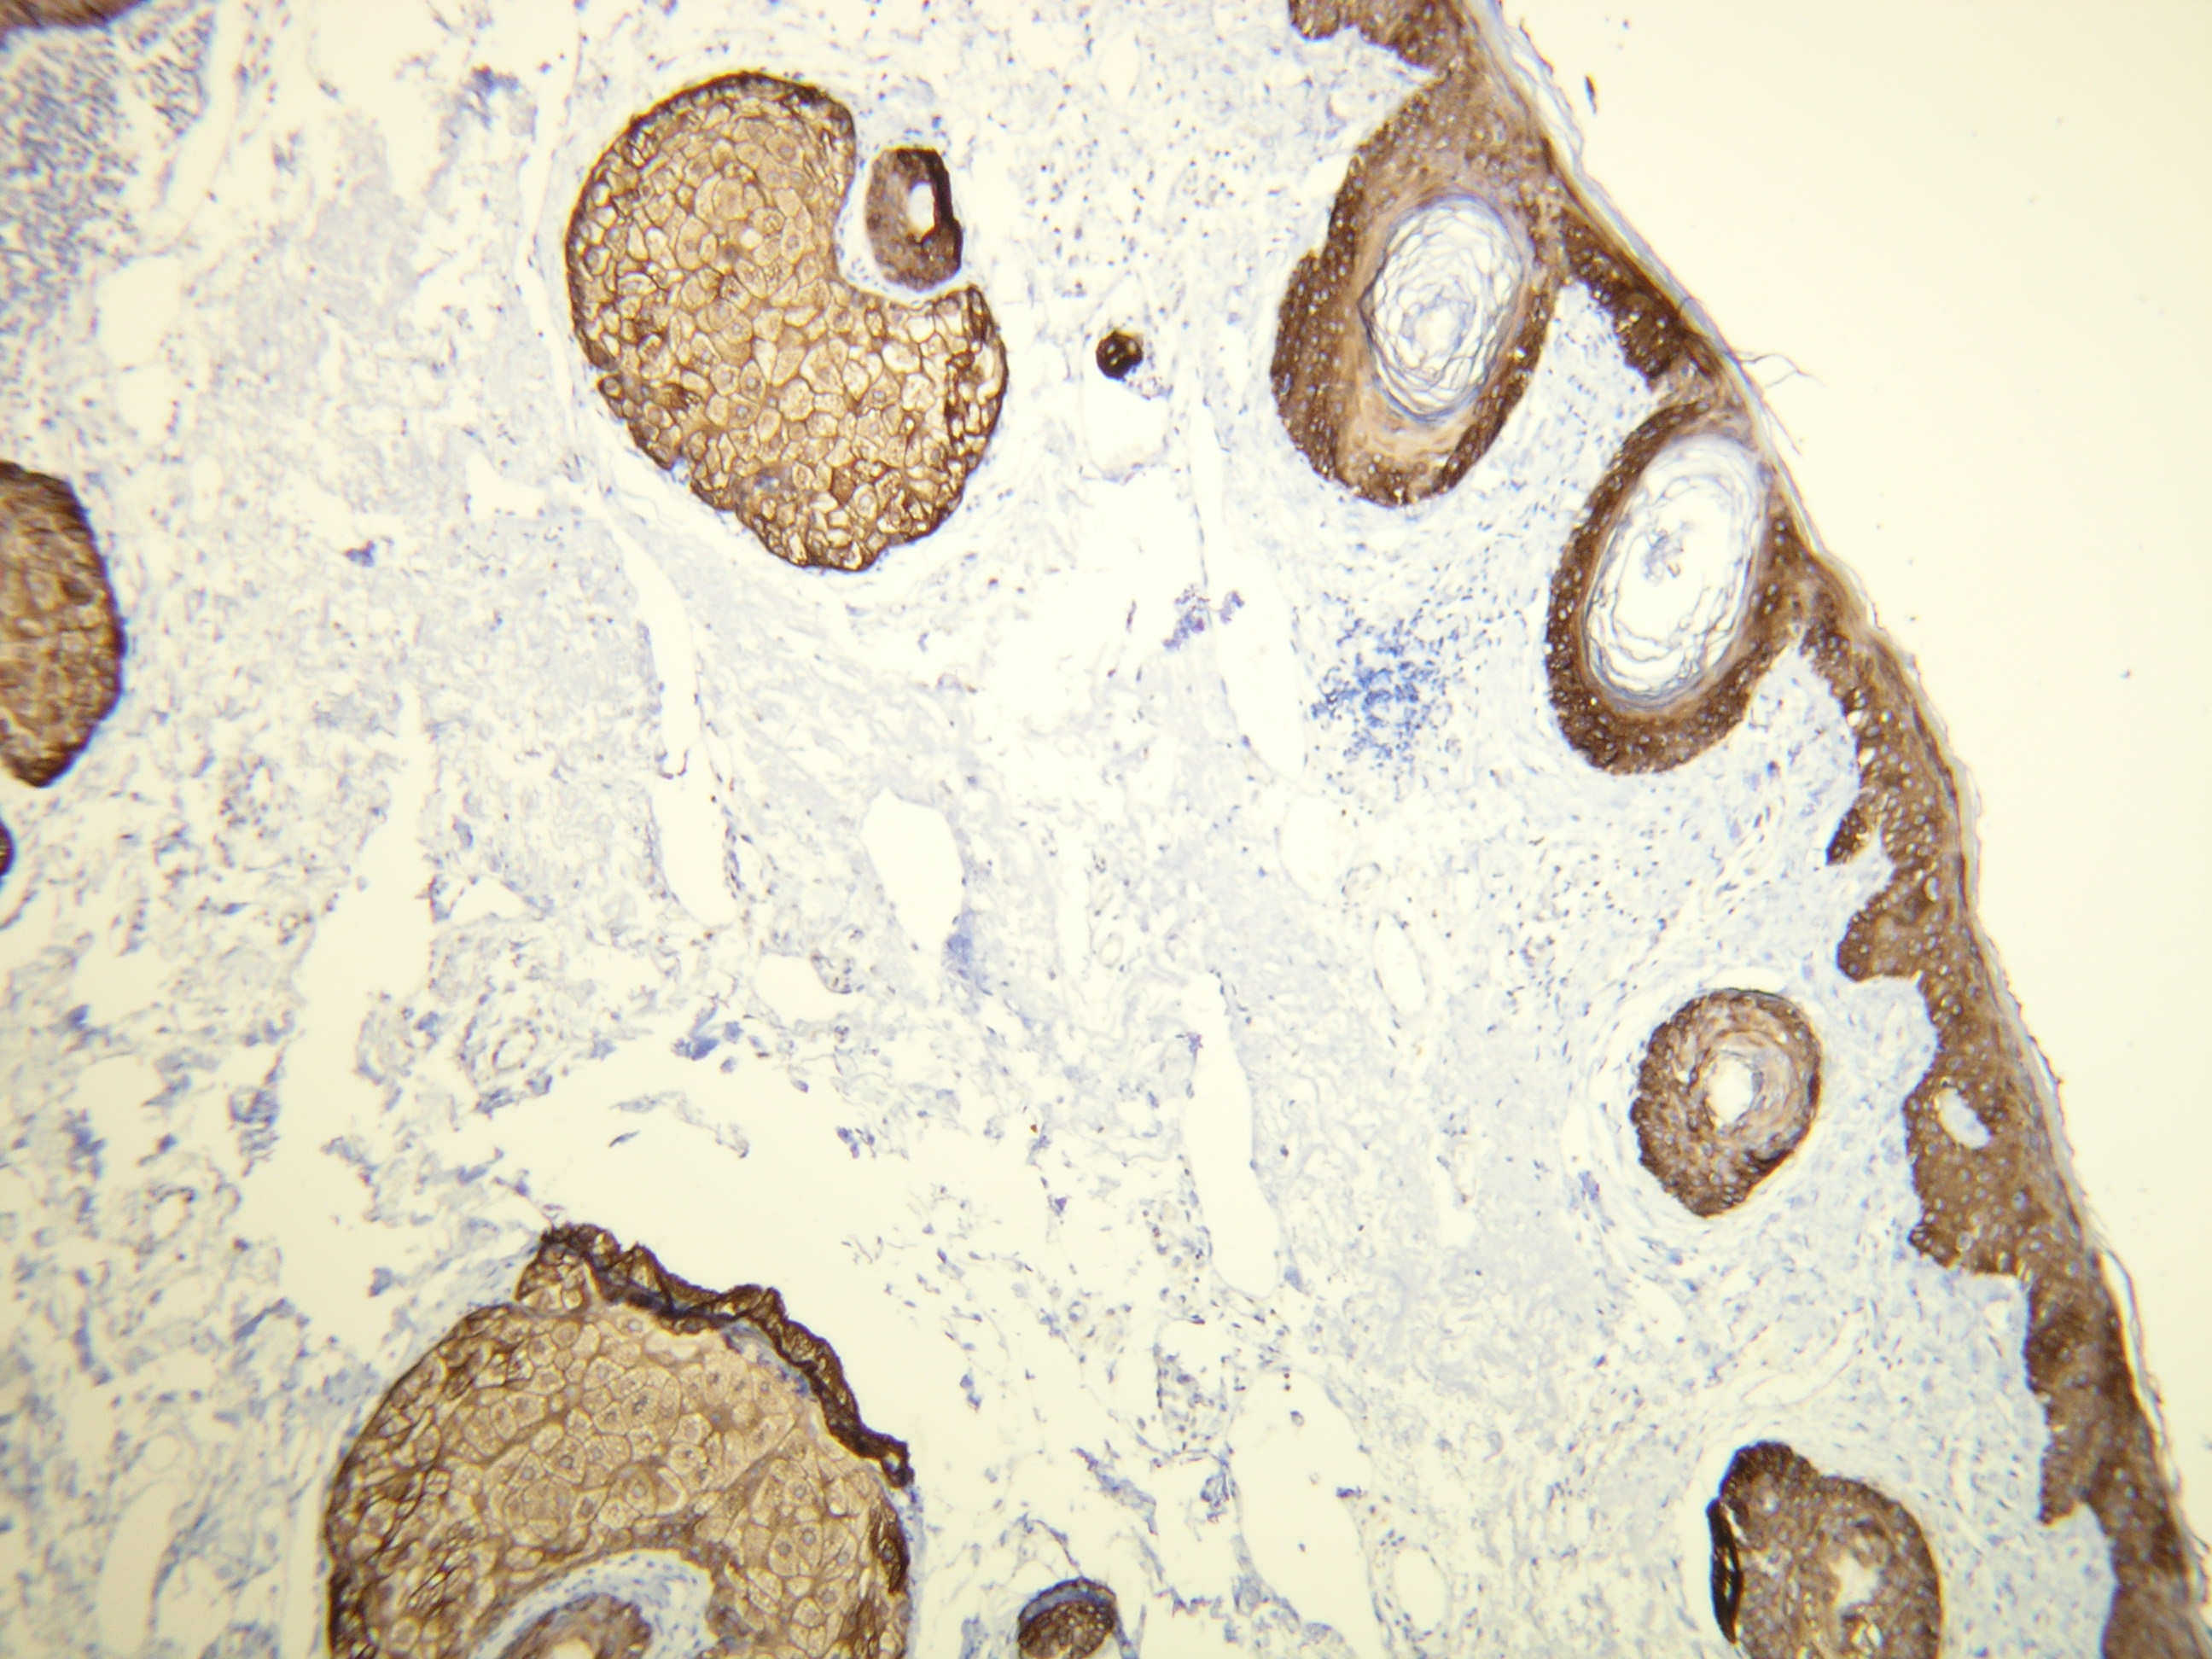

Anti-Cytokeratin 14

Peptid derivovaný z C-konca ľudského Cytokeratín 14 proteínu. Protilátka rozpoznáva epitop umiestnený medzi Val455 - Lys471.

IHC-P, riedenie 1:100

db099a db099b db099c